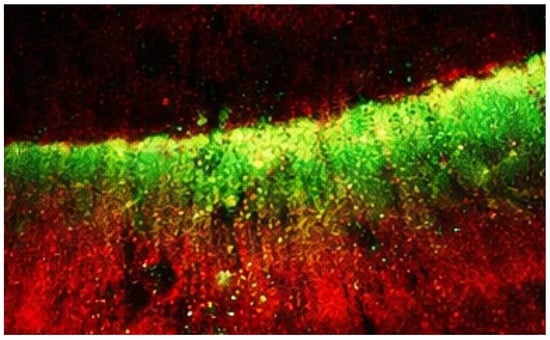

After infiltration, specimens were sectioned longitudinally through the lesion area. Penetration depth was evaluated using confocal laser scanning microscopy (Leica TCS SP8, Wetzlar, Germany) after staining the infiltrant with a fluorescent dye (Figure 2).

Figure 2.

Penetration depth evaluation using confocal laser scanning microscopy. The infiltrant labeled with a fluorescent dye appears as the green signal, indicating the extent of penetration into the lesion body. The red background corresponds to the tooth structure stained with a counterstain, allowing differentiation between infiltrated and non-infiltrated areas.

Penetration was measured at three standardized points per specimen, and mean values were calculated. All measurements were performed by an examiner blinded to the experimental group allocation to minimize measurement bias.